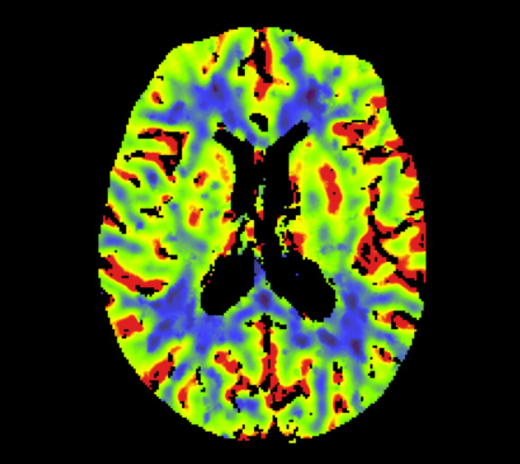

• 脑神经科:脑部微细血管显影更清晰,提升中风及复杂病变诊断的准确度。

脑灌注